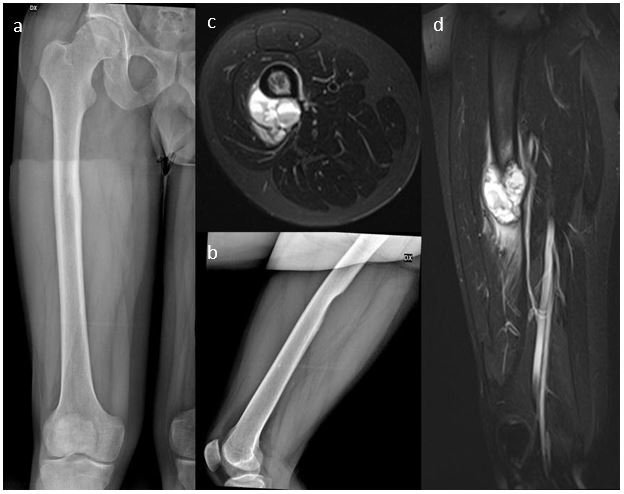

The patient was admitted to radiology department to make a plain-X-rays. Radiograph demonstrated an expansive bone mass in the posterior diaphyseal of the right femur characterized by sharp margins, cortical erosion phenomenon, without any periosteal shell. Basing on these findings the patient underwent MRI scan that confirmed a rounded-shape bone lesion localized in the diaphyseal of the right femur extending along the posterior and lateral surface of the bone. In axial acquisitions the lesion was localized in externally to the cortex and involves the smooth tissue around the femur; it showed a heterogeneous signal both in T1 and T2 sequences with a septations and polycystic appearance associated with blood-filled spaces with fluid-fluid levels. After ev gadolinium administration there was an enhancement of lesion wall and septations. The lesion also determined erosion of the outer cortex of the femur and oedema both of perilesional soft tissue and bone marrow. The MRI scan in consideration of characteristic polycystic aspect with fluid-fluid levels suggested the diagnosis of ABC although its localization was atypical (Figure 1).

Figure 1a-1d: 1a and 1b represent preoperative anteroposterior and lateral radiographs of the right femur. Lateral view shows an oval cortical erosion in the posterior diaphyseal region with indefinite borders between the bone and the surrounding soft tissue, without any periosteal shell. Axial and coronal STIR sequences (1c and 1d) demonstrate a large multi-locular cystic lesion in subperiosteal location, exceeding in the soft tissues with peri-tumoral soft tissue edema. Note fluid-fluid levels and reactive bone marrow edema.